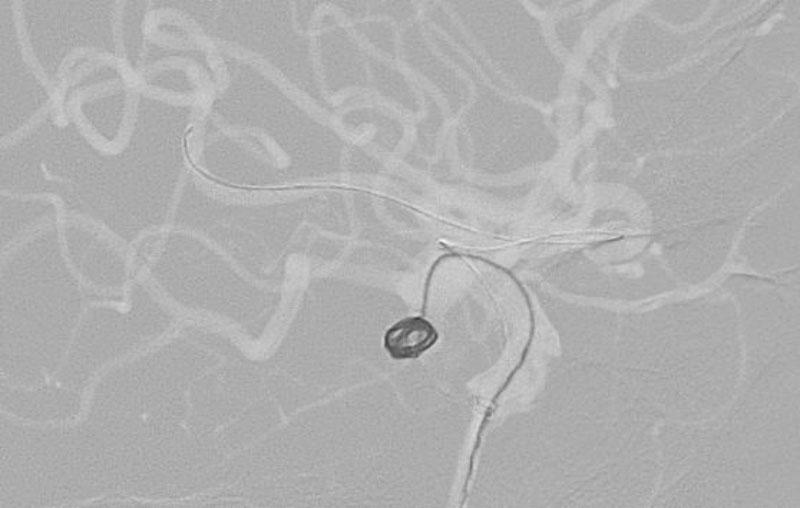

'26年4月

左椎骨動脈後下小脳動脈分岐部動脈瘤

70代

院内外来

No.1628 手術前

No.1628 手術中

No.1628 手術後